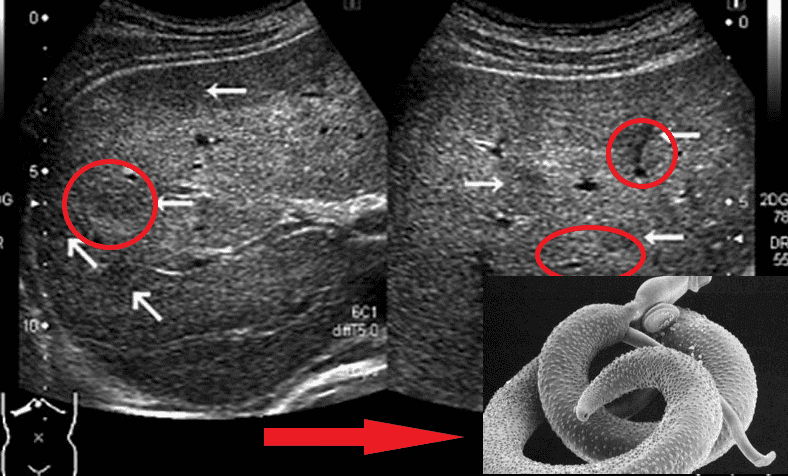

На фото нижче можете побачити знімок кишечника. Пацієнтка померла від раку кишківника, спричиненого паразитами. Паразити отруюють здорові клітини своїми токсинами, через що вони змушені перероджуватися, змінювати свою структуру. І перероджуються вони саме в ракові клітини, які агресивніші й здатні протистояти паразитам. Але для людини ці клітини згубні. Пухлина швидко розвивається і метастазує. Людина гине протягом лічених місяців.

"Ходи" паразитів у просвіті кишечника